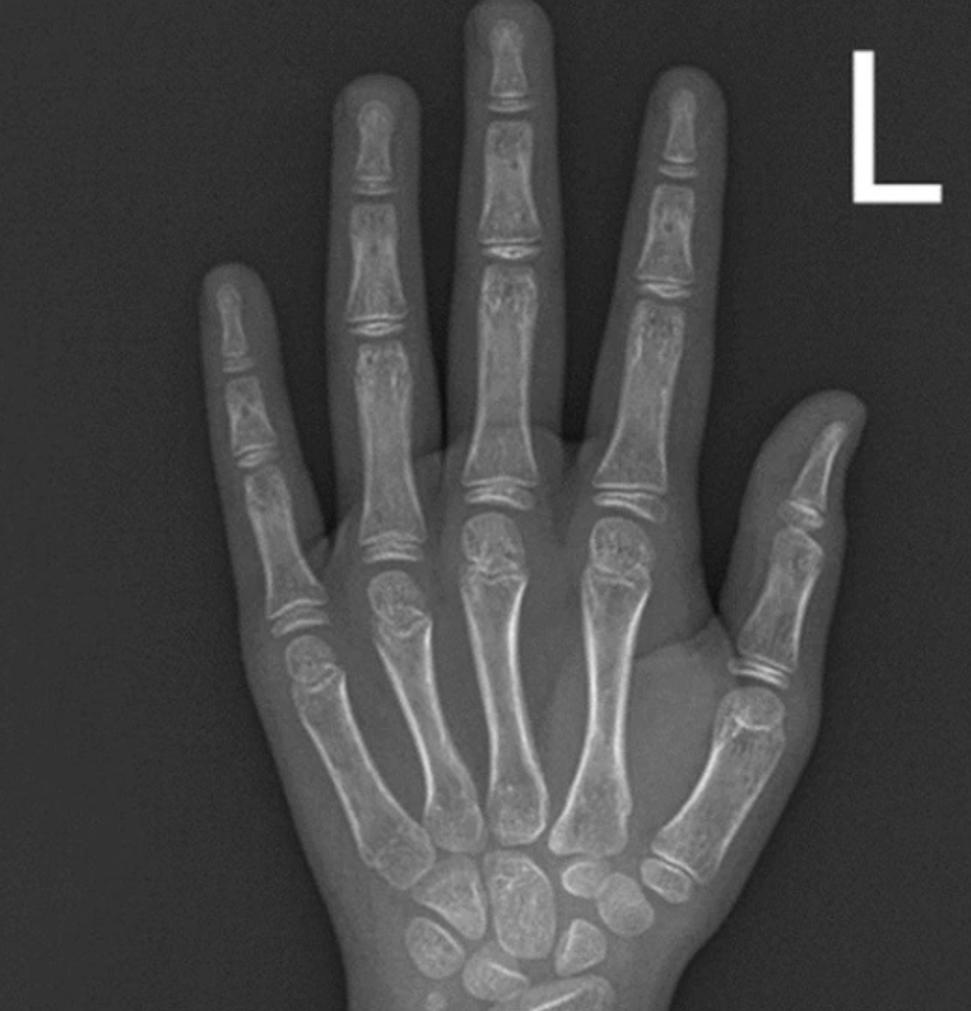

Kết quả cận lâm sàng X-quang cho thấy tuổi xương của bé tương đương với trẻ 8 tuổi. Kết quả xét nghiệm nội tiết cho thấy trẻ bị dậy thì sớm.

Hình ảnh phim chụp xương trẻ tương đương với trẻ 8 tuổi (ảnh BSCC).